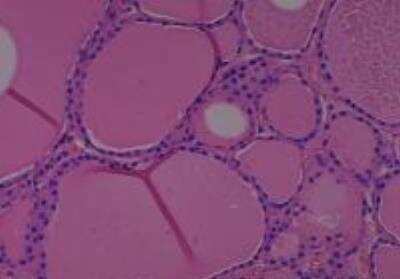

Hematoxylin & Eosin Stain: Human Common Tissue MicroArray (Normal Adjacent) [NBP2-30215] - 102. Stomach